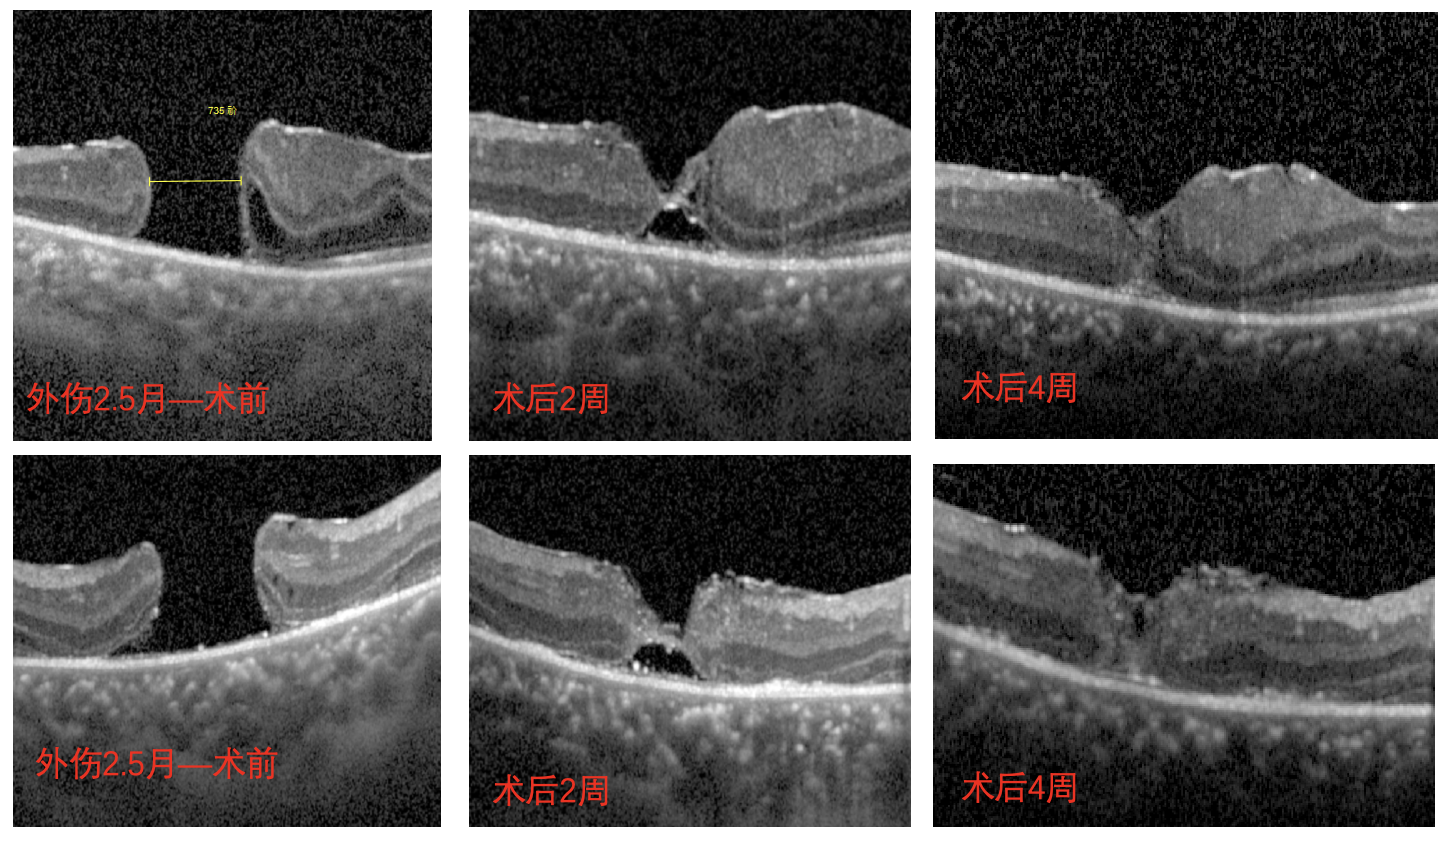

但術(shù)后一個月復(fù)查時發(fā)現(xiàn),南南的眼底恢復(fù)情況并不好,檢查時還可見黃斑處的裂孔,并且裂孔越來越大,演變成難治性黃斑裂孔。

經(jīng)過完善的術(shù)前檢查和評估后,李海波博士后用創(chuàng)新術(shù)式——剝除黃斑裂孔周邊殘余的內(nèi)界膜組織,通過利用黏彈劑固定翻轉(zhuǎn)的內(nèi)界膜瓣為南南進(jìn)行治療。術(shù)后24小時復(fù)查時,南南黃斑處的裂孔已實現(xiàn)愈合,視力也得到了明顯的改善,現(xiàn)已康復(fù)出院。